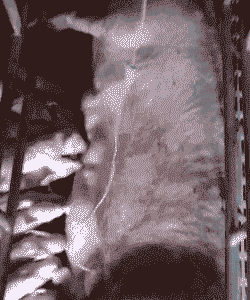

静脉输液

第一瓶:0.9%氯化钠溶液500ml+头孢噻呋钠5毫克/公斤体重;

第二瓶:5%葡萄糖溶液500ml+鱼腥草注射液20ml;

第三瓶:甲硝唑溶液150ml,加温35℃后静脉输液,连用2-3天。